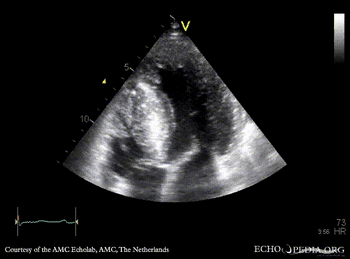

E00513.gif E00514.gif

PSAX: severe concentric hypertrophy of left ventricle PLAX with Color Doppler: high velocity turbulent flow in LVOT, moderate mitral regurgitation